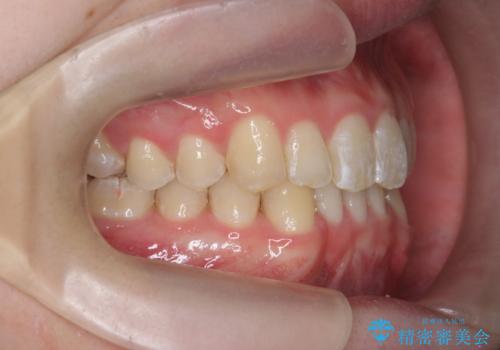

クロスバイト・歯並びが原因の歯肉退縮歯、矯正治療による審美性の改善

- 前歯の歯並び、下顎前歯の歯ぐきの下がり(歯肉退縮)の改善を求めて来院されました。

歯肉退縮の根本的な原因はすれ違った噛み合わせによる為害性のある咬合状態にあるため、歯肉退縮に対し結合組織の移植術を行うのではなく当該歯を抜去し部分矯正を含めた治療計画を立案します。

矯正治療を行ったことで、噛み合わせが安定し審美性も機能性も向上することができました。